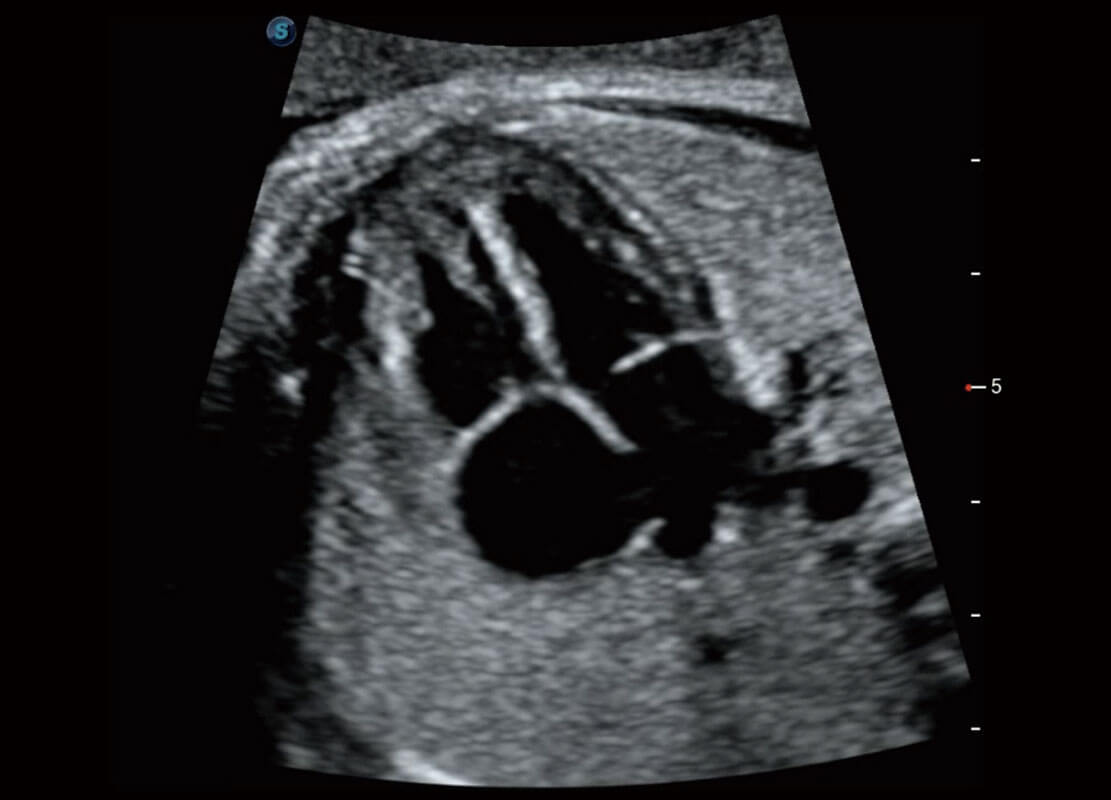

P60搭载一系列胎儿心脏成像技术,实现精细的胎儿心脏评估。

四腔切面

四腔心血流

右室双出口

胎心容积成像